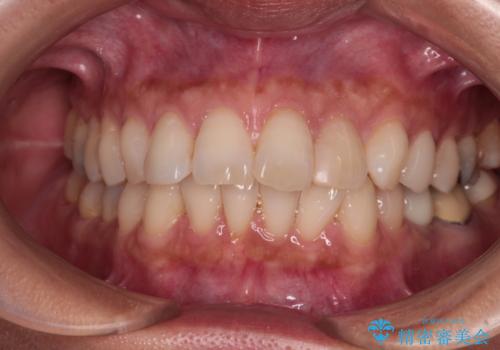

1日22時間の装着時間をしっかり守ってくださったので、1年程度で治療を終えることができました。

1セットのマウスピースで概ね治療を終えたのですが、前歯僅かな叢生が残ったため、2セット目のマウスピースで仕上げました。

気にしていた口元の印象が改善され、患者様には大変満足していただきました。